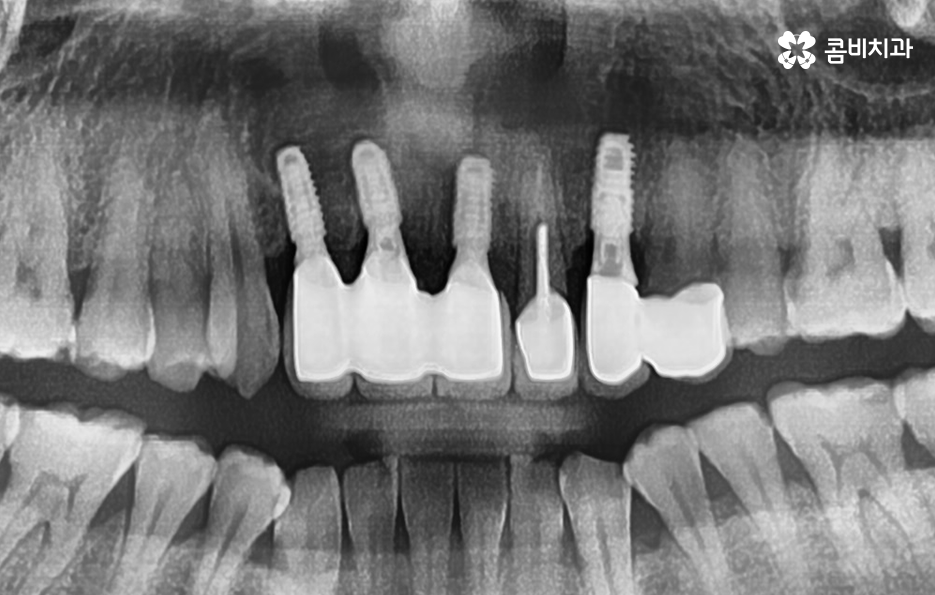

이렇게 앞니가 상실되면 심미적, 기능적 불편이 크기 때문에 많은 분들이 앞이빨 임플란트 과정을 거치게 되는데 앞니 임플란트는 어금니와는 다른 부분에서 좀더 정교한 치료가 필요하며 앞니 부위는 뼈가 얇고 심미성이 중요한 부위라는 점에서 잇몸 라인, 앞니의 각도, 심미성, 주변 치아와의 조화까지 모두 맞아야 자연스럽게 보이므로 정교한 치료의 중요성이 더 높은 부위라고 할 수 있어요

그리고 앞니는 씹는 힘이 약해 보이지만 가로 방향 힘이 많이 가해져서 임플란트에 부담을 주기 쉽고 앞니 상실의 원인이 치주염이라면 뼈가 많이 녹아 있는 경우가 많아 뼈 이식이 필수적인 상황이 자주 생기므로 앞이빨 임플란트 과정에서 주의해야 할 점들에 대해 잘 알고 접근하는 것이 중요한 거예요

또한 앞니는 잇몸의 모양이 심미성에 큰 영향을 주는데, 잇몸이 얇으면 임플란트가 비쳐 보이거나 잇몸 라인이 붕괴될 위험이 있어서 이런 경우에는 잇몸 두께를 보강하는 잇몸 이식술이 필요할 수 있으며 앞이빨 임플란트 과정 뿐 아니라 치료 후에도 잇몸 관리는 앞니 임플란트의 수명, 심미적인 유지에 있어서 중요한 요소라고 볼 수 있었어요

앞니는 사람들에 따라서 상실 원인이 다르고 현재의 잇몸 및 전신건강 상태가 다르며 특히 중년이후에는 기존의 보철물이 노후되거나 치주염으로 인해 치아를 상실하는 경우도 많기 때문에 앞이빨 임플란트 과정이라서 해서 단지 빠르게 치료하는 것만이 중요한 것이 아니라 장기적인 안정성 등을 충분히 고려한 치료 계획이 중요하므로 경험 많은 치과의사와 충분히 상의하고 정밀검진 결과를 토대로 나에게 맞는 치료 계획 그리고 사후관리까지 고려한 장기적인 유지까지 고려하여 판단하시길 바라고 있어요